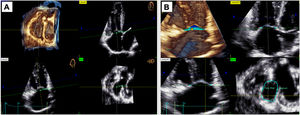

MethodsThis prospective case-control study included children with CHD who were divided into 2 groups based on the type of RV overload. Using 3D-TTE, we assessed the dimensions of the right chambers, the surface area, and the tenting volume of the TA, and analyzed the correlation among these measurements.

ResultsA total of 90 patients were enrolled: 30 with pretricuspid overload (atrial septal defect and partial anomalous pulmonary venous connection), 33 with posttricuspid overload (pulmonary regurgitation after RV outflow tract surgery), and 27 healthy controls. 3D TA surface area was larger in the pretricuspid group than in the posttricuspid group (median 6.60cm2/m2 vs 5.16cm2/m2; P=.01) and was correlated with right atrial (RA) volume (P=.0001, r=0.66) and RA surface area (P<.0001, r=0.74) in the pretricuspid group. The tenting volume was greater in the posttricuspid group than in the control group. The 3D TA surface area and tenting volume were not correlated with RV end-diastolic volume.

Conclusions3D modeling of the TA using 3D-TTE is feasible and provides insights into TA remodeling in different RV overload conditions. RA volume and surface area are key determinants of TA size, which could have an impact on therapeutic strategies in patients with tricuspid regurgitation.